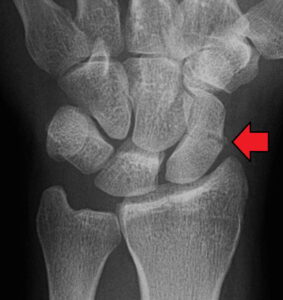

Imaging

• X-ray at least AP and lateral

• Consider MRI as first line for suspected scaphoid fractures following thorough clinical examination (3).

• CT scans are also often used to help further visualise the fracture and are recommended by the BSSH pathway (see (4)).

• Important to note:

• Location of fracture (distal pole, waist, proximal pole)

• Any displacement

• Any articular surface involvement

• Associated peri-lunate dislocation